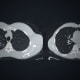

Mount Sinai Health System is taking a systematic approach to addressing incidental lung nodules. It includes using natural language processing to scan all Mount Sinai Morningside and Mount Sinai West chest-related radiological reports for any reference to nodules—including related terminology such as lesions and nodularity.